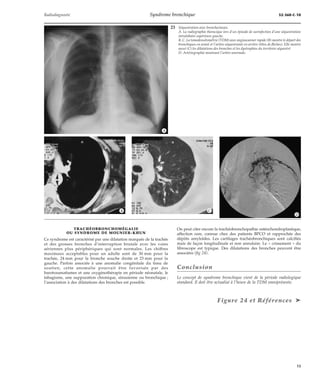

3 Syndrome bronchique en radiographie thoracique. Distension thoracique avec ho-rizontalisation

des coupoles ; aspect en « rail » des parois bronchiques des lobes infé-rieurs

(étoiles) ; majoration d’épaisseur pariétale bronchique avec l’aspect A2B2 dit en

« jumelle borgne » (flèches).

Le cliché peut donc être normal au début ou au contraire caricatural

dans les formes évoluées (fig 3, 4). Le malade peut entrer dans la

1 Syndrome bronchique en radiographie thoracique. Radiographie thoracique de face

présentant des signes de distension pulmonaire avec visualisation et déplacement des

lignes médiastinales commissurales (triples têtes de flèches) et un trouble ventilatoire

collapsique en lobaire inférieur gauche (étoile, doubles flèches).

2 Syndrome bronchique en ra-diographie

thoracique.

Radiographies thoraciques de face

(A) et de profil (B) présentant une

visualisation en « rails » épaissis

des parois bronchiques de la pyra-mide

basale gauche dont l’éventail

est anormalement resserré de profil

(têtes de flèches). On note un as-pect

dit en « rayon de miel » loca-lisé

de la base droite lié à d’éven-tuelles

dilatations des bronches

(étoile) que l’on retrouve de profil

en lobaire moyen.

*A *B